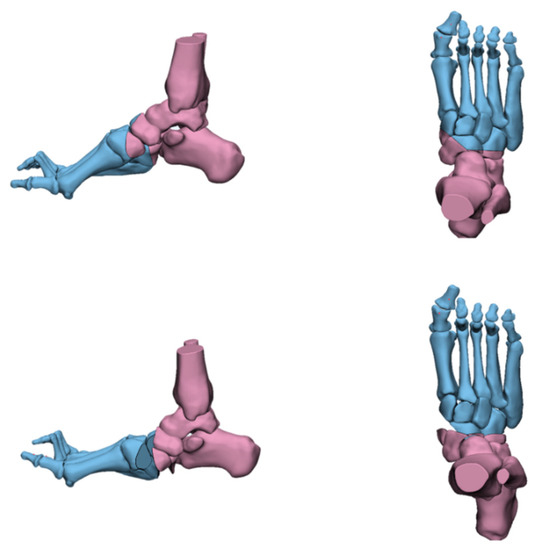

4.2. Radiological Evaluation

- An, T.; Haupt, E.; Michalski, M.; Salo, J.; Pfeffer, G. Cavovarus With a Twist: Midfoot Coronal and Axial Plane Rotational Deformity in Charcot-Marie-Tooth Disease. Foot Ankle Int. 2022, 43, 676–682. [Google Scholar] [CrossRef]